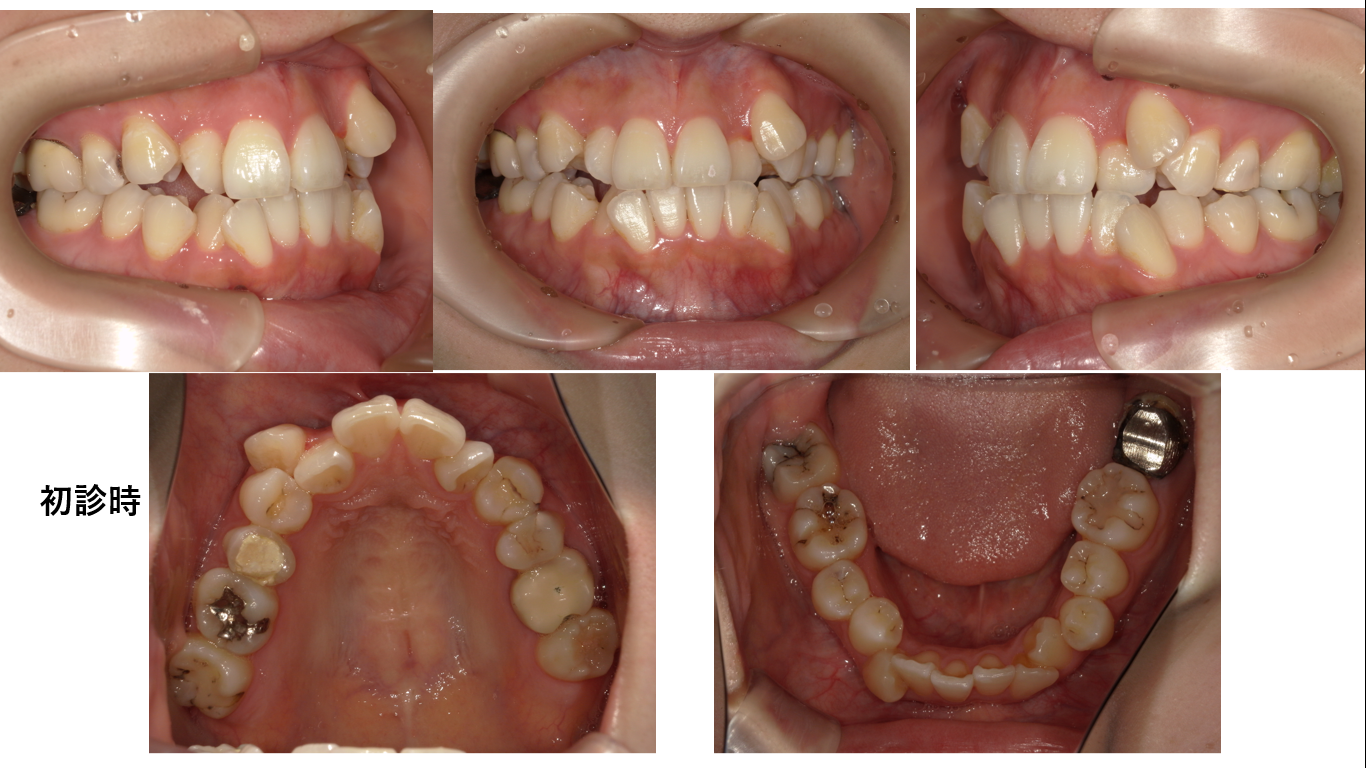

矯正症例139 AngleⅠ級叢生、下顎8番埋伏歯の牽引

初診時30歳、抜歯部位:上顎左側5番、下顎右4番,左側5番、下顎右側7番、治療期間3年7か月

、治療費総額113万(税込み)

上顎右側犬歯は抜歯されていました。初診の下顎右側7番が銀歯ですが、動的治療終了時の下顎右側7番は白い歯です。これは銀歯を白いに歯に替えたのではありません。根管処置された下顎右側7番のメタルコアが極めて大きく予後不良と判断され抜歯されたからです。抜歯の後、埋伏歯である右側8番は牽引されて7番の位置へ排列されました。

下顎右側8番埋伏歯を牽引するのに2年6か月かかりました。